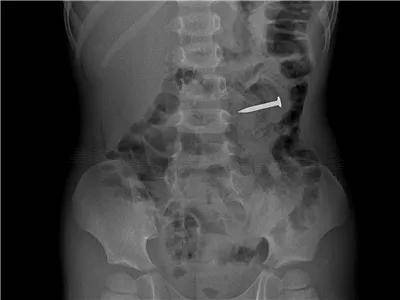

4岁·铁钉

当天11点左右误吞铁钉一枚,约4cm大小,铁钉已入胃肠深处。这种尖锐的钉子最是危险,随时可能戳穿消化道!